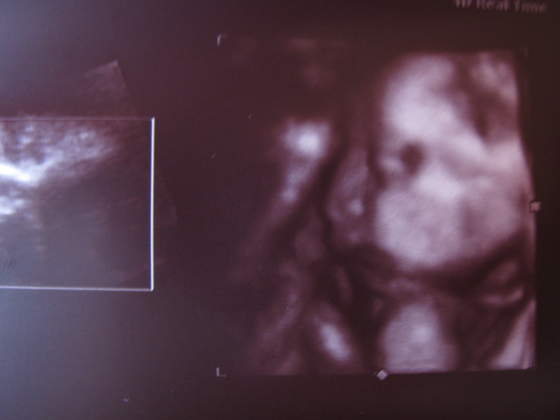

paula-śliczna duża babka i te murzyńskie usta ech!

ale lekarka mnie uspokoiłanadika wstydziosze z Natanka:-)Cudeńko z piękną wagąA co lekarz mówił na tą pępowinę?